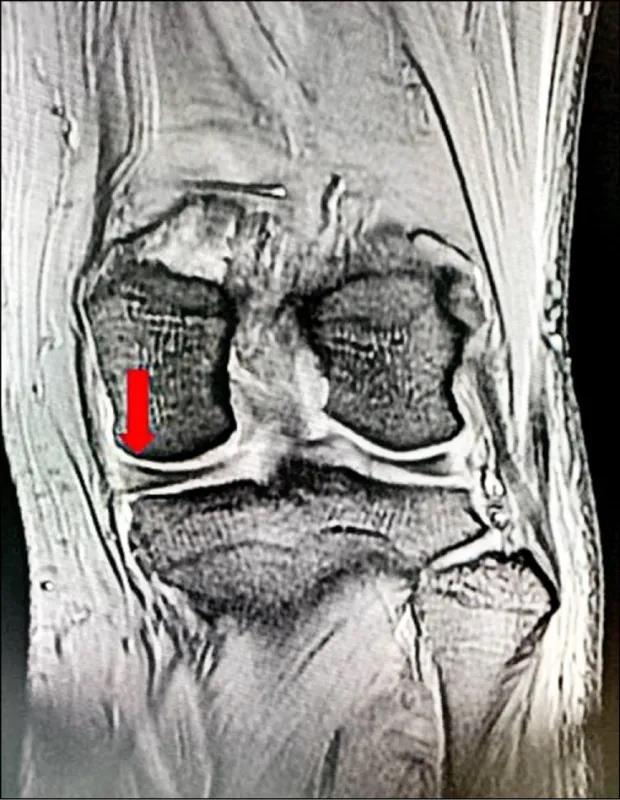

▲核磁共振检查显示,内侧半月板破裂(箭头处)

理学检查发现,她的关节内侧明显压痛,建议做核磁共振(MRI)检查,才诊断出原来是膝盖半月板破裂,接受了关节镜微创手术后,慢慢回复正常生活。

中老年人膝盖疼痛,一个要想到的是退化性关节炎造成软骨磨损,但是有少部分人因为膝盖受到过大扭转的力量,可能会造成半月板的破裂,疼痛的位置好发于膝关节的内外侧关节交界处,蹲下时,疼痛会加剧,但是这样的症状在临床上有时很难跟软骨退化磨损造成的疼痛区分,因此需要MRI检查来帮助诊断。